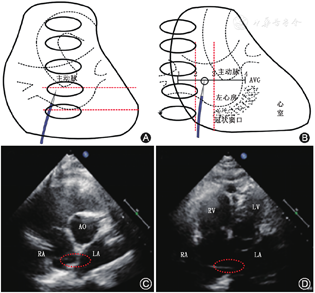

在正位X线透视下,房间隔穿刺鞘沿配套导丝送至上腔静脉,退出导丝后送入连接造影剂的穿刺针,距鞘管头端1 cm处固定,在X线透视下缓慢回撤,同时将穿刺鞘和穿刺针由12点钟方向逐渐指向5点钟左右方向的房间隔部位(根据心房大小调整方向),后前位(postero-anterior,PA)时鞘尖以位于左心房影下缘上半个至一个椎体高度为宜(图1A)。当鞘尖顶住房间隔后,在右前斜位(right anterior oblique,RAO )45°适当再次调整穿刺点至左心房后缘前半个至一个椎体为宜(图1B),以穿刺针及鞘管远段弧度消失呈直线状或接近直线状为理想穿刺点。

TTE下可观察到穿刺鞘尖端抵在房间隔上形成的"帐篷顶"现象。对于大多数患者穿刺的合适位置:(1)胸骨旁主动脉短轴切面,位于房间隔下端的中下1/3处(图1C);(2)心尖四腔心切面,位于房间隔中部(图1D)。